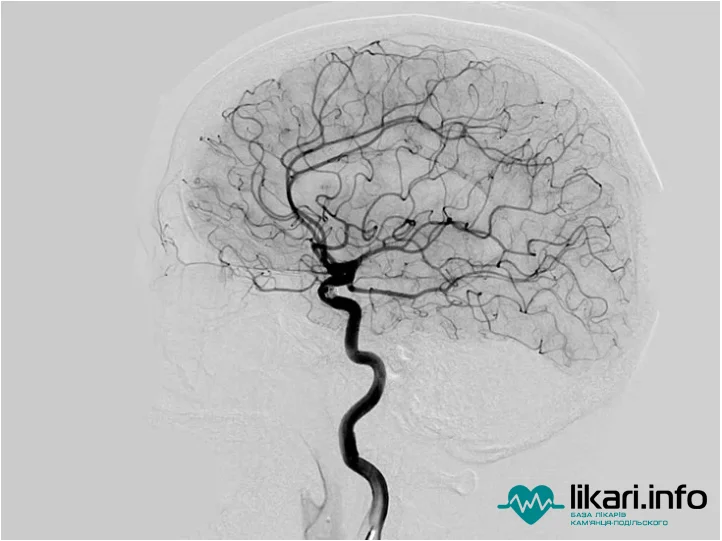

Ангіографія судин головного мозку: можливості методу та підготовка

Ангіографія судин мозку — високоефективний метод діагностики, який широко застосовується в кардіології та неврології. Завдяки цьому дослідженню лікарі можуть точно визначити область закупорки, розташування тромбу, пухлини або звуження судин, оцінити стан аневризми та виявити приховані кровотечі.

Процедура полягає у рентгеноскопічному обстеженні із введенням контрастної сполуки на основі йоду. Це дозволяє «підсвітити» судини на знімку та побачити будь-які структурні зміни.

За даними ресурсу RadiologyInfo (спільного проекту RSNA та ACR), церебральна ангіографія залишається найбільш детальним методом оцінки кровоносних судин мозку. Сучасні протоколи наголошують, що вона часто допомагає уникнути відкритої хірургічної операції завдяки можливості проведення малоінвазивних інтервенцій під час самої діагностики.